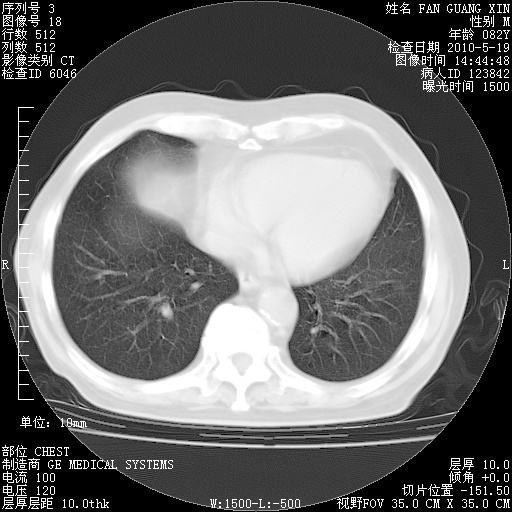

复查肺部CT,明显好转。为什么发热呢?

治疗3周后的肺部CT

治疗3周后的肺部CT纵隔窗